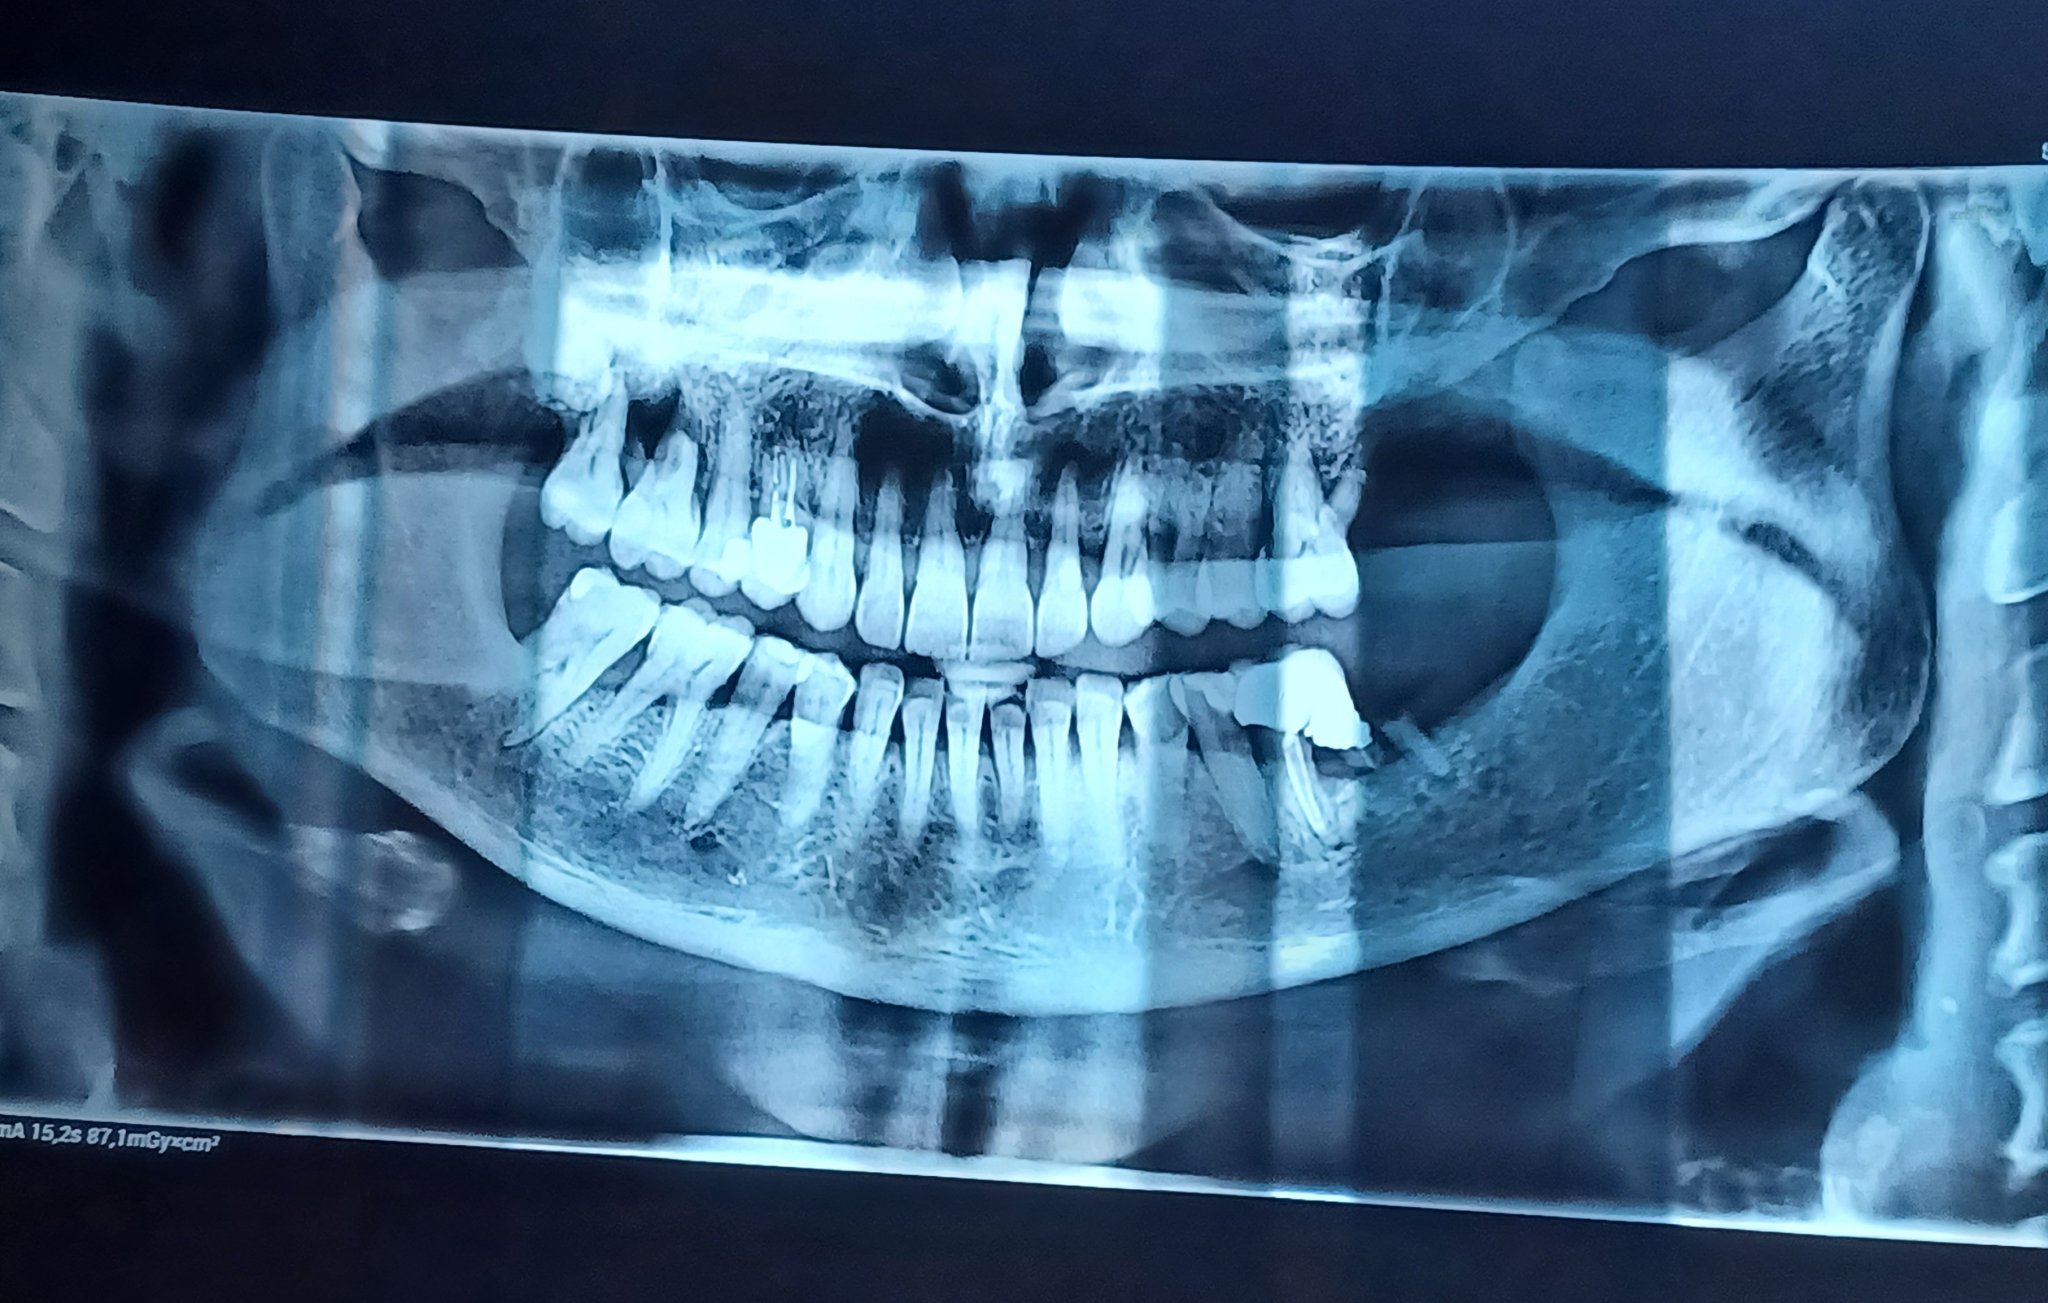

Зависи колко е костта, ако имате снимка можете да я прикачите или да я изпратите на лично съобщение.

За горе вляво говорим, нали? Защото 7ми зъб има вляво, а вдясно няма (освен, ако не е обърната снимката). Честно казано не се вижда добре, ако можете да снимате само зъбите, които за проблемни. Просто не мога да видя нивото на костта заради лошото качество.